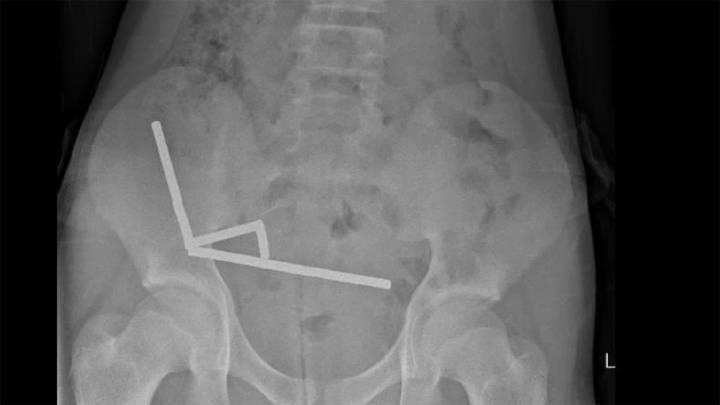

After four days of stomach pain, the 13-year-old boy was admitted to Tauranga Hospital on New Zealand's North Island, where doctors discovered the magnets had joined together to form four chains inside his intestines.

Surgeons extracted the magnets and removed parts of the boy's damaged intestines, according to a report by doctors at the hospital, published Friday in the New Zealand Medical Journal .

The boy, who was not identified in the report, had swallowed “approximately 80–100 5x2mm high-power neodymium magnets” a week prior to his hospitalization, the doctors said. He was discharged after s